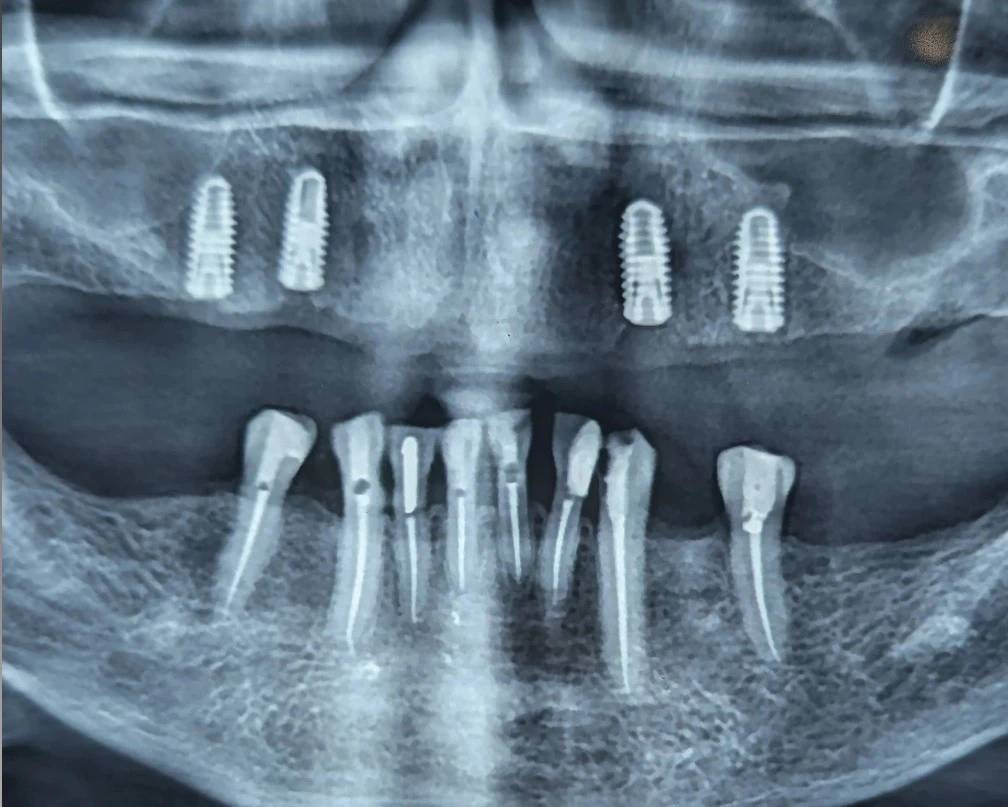

بیمار با هدف انجام اوردنچر فک بالا مراجعه کرده بود.

ایمپلنتهای ماگزیلا قبلاً در مرکز دیگری قرار داده شده بودند و طرح درمان اولیه توسط من ارائه نشده بود.

در نگاه اول، تعداد ایمپلنتها برای اوردنچر قابل قبول به نظر میرسید؛

اما دو ملاحظه مهم باعث شد ورود به فاز پروتز پذیرفته نشود.

اما ملاحظه اصلی، وضعیت اکلوژن بیمار بود.

در فک پایین اکلوژن خلفی مؤثری وجود نداشت و تماسها عمدتاً در ناحیه قدامی متمرکز میشدند.